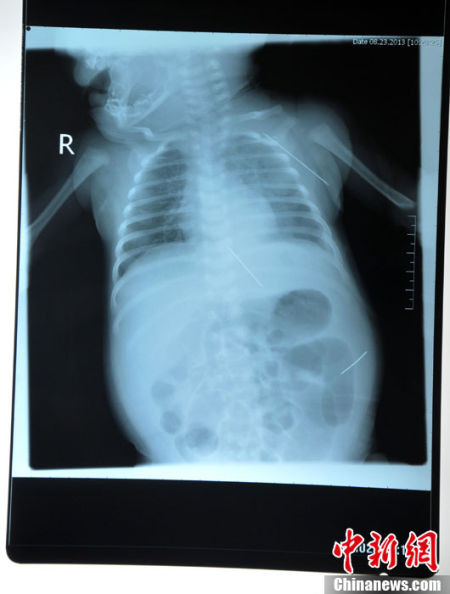

Sau khi được chuyển đến một bệnh viện tại tỉnh Hắc Long Giang, các bác sĩ đã tiến hành chụp X-quang và phát hiện 3 chiếc kim khâu dài khoảng 4,5 cm đâm vào khoang bụng và vùng dưới nách của bé gái.

Ảnh chụp X-quang cho thấy vị trí của chiếc kim khâu.